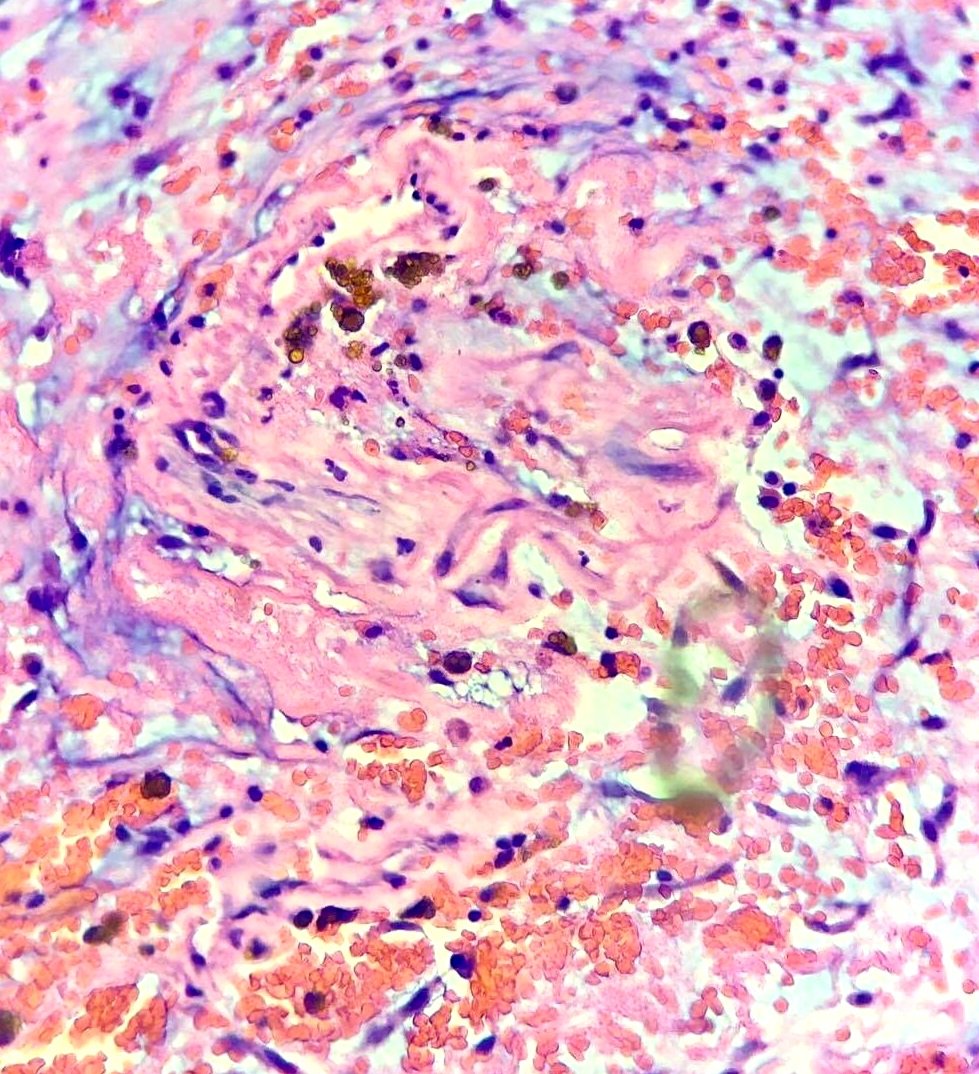

Left Atrial Myxoma causing Acute Ischemic Stroke in an 8 year old girl. Atrial myxomas are uncommon in the pediatric population but are very important due to pursuant atrioventricular valve obstruction and systemic embolic events. #cardiacpath #CVpath 🔬♥️

Left Atrial Myxoma causing Acute Ischemic Stroke in an 8 year old girl.

Atrial myxomas are uncommon in the pediatric population but are very important due to pursuant atrioventricular valve obstruction and systemic embolic events.

#cardiacpath #CVpath